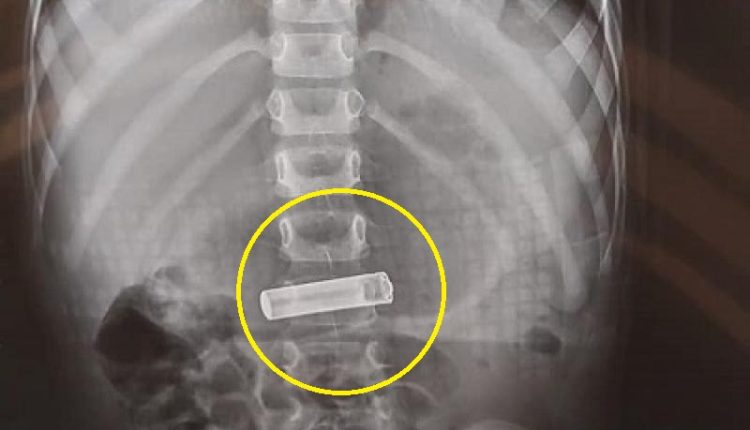

وادخل الطفل بعد شعورة بالآلم إلى الطوارئ وقامت المستشفى بعمل فحوصات وصور ليتبين لهم ان الطفل ابتلع بطارية ريموت .

وتدخل الفريق الطبي على الفور وتم دخول الطفل إلى وحدة التنظير واستخراج البطارية .